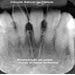

Lesões do Periápice e Periodonto